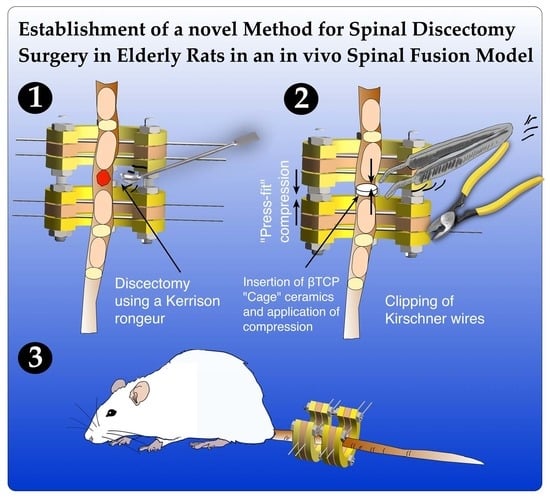

Establishment of a Novel Method for Spinal Discectomy Surgery in Elderly Rats in an In Vivo Spinal Fusion Model

2. Experimental Design

3.4. Surgical Procedure

-

- CRITICAL STEP Insert the k-wires in a slightly posterolateral direction to avoid damaging the vessels running laterally to the vertebrae.

-

- CRITICAL STEP Wound closure should be performed in a two-step process with subcutaneous closure using 4.0 Vycril and cutaneous closure with 5.0 Ethilone to ensure complete wound closure and prevent animal wound biting and wound infection.